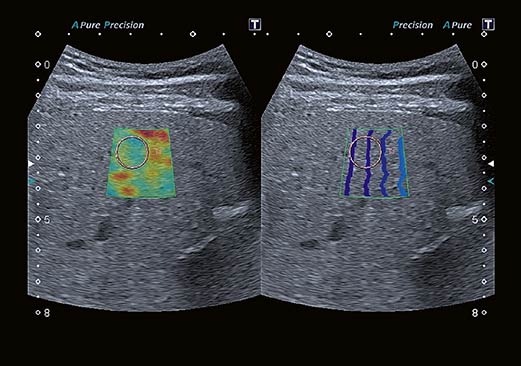

Технология сдвиговых волн Canon Medical Systems обеспечивает количественное измерение и динамическое визуальное отображение жесткости ткани в различных клинических условиях, начиная от брюшной полости и заканчивая исследованиями мелких деталей. Высокоточный и воспроизводимый инструмент обеспечивает полностью интегрированные измерения и отчеты для полной интеграции в ваш клинический рабочий процесс.

Технология эластографии с функцией сохранения исходных данных в формате RAW предназначена для локализации и оценки жесткости пальпируемых образований с непревзойденной точностью.

Эластография в реальном времени. Наше комплексное решение для эластографии с функциональностью необработанных данных помогает локализовать и оценивать ощутимые массы с высокой точностью, чувствительностью и воспроизводимостью в широком диапазоне клинических условий. Различные параметры эластичности ткани могут быть определены количественно или иметь цветовую кодировку на параметрических изображениях, делая подозрительные изменения ткани количественными и видимыми на ультразвуковом изображении.

Индикатор качества помогает вам правильно подать давление на датчик, гарантируя, что вы всегда получаете надежные результаты.